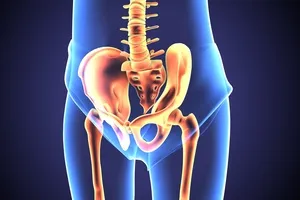

좌골신경통은 좌골신경이 압박되거나 자극받아 발생하는 통증을 말합니다. 좌골신경은 인체에서 가장 길고 큰 신경으로, 허리 아래쪽에서 엉덩이를 지나 다리 뒤쪽까지 이어집니다.

주로 허리 디스크, 척추관 협착증, 엉덩이 근육 문제 등이 원인이 됩니다. 증상이 심해지면 일상생활에 큰 불편을 초래할 수 있으니 조기 대처가 중요합니다.